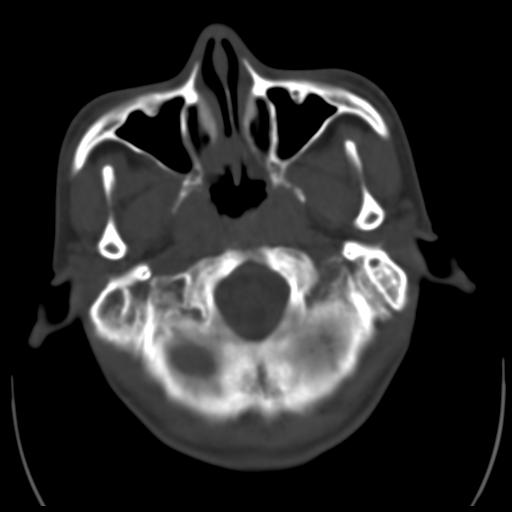

35m 鼻子时不时流血,头及右侧面部痛,颈部淋巴结未见明显大

骨窗

考虑鼻咽癌侵犯颅底并突入右侧鼻腔;双侧中耳乳突炎。

蝶窦,后组筛窦及鼻咽部团块状软组织影,骨壁破坏,病变较广泛。考虑恶性肉芽肿。建议活检。

颅底骨质明显破坏 支持鼻咽癌 但病灶的边缘毛糙 不能除外炎性

蝶窦,后组筛窦及鼻咽部团块状软组织影,骨壁破坏,病变较广泛。考虑炎性肉芽肿性病变可能。建议活检。